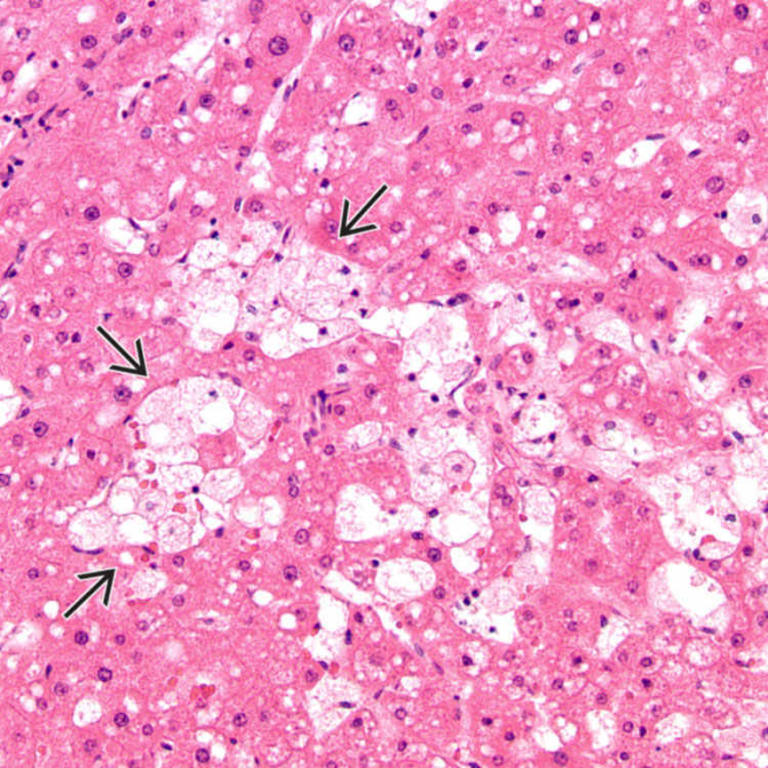

Болезнь Нимана-Пика Тип А: Симптомы и лечение

Раздел: Визуальный дайджест